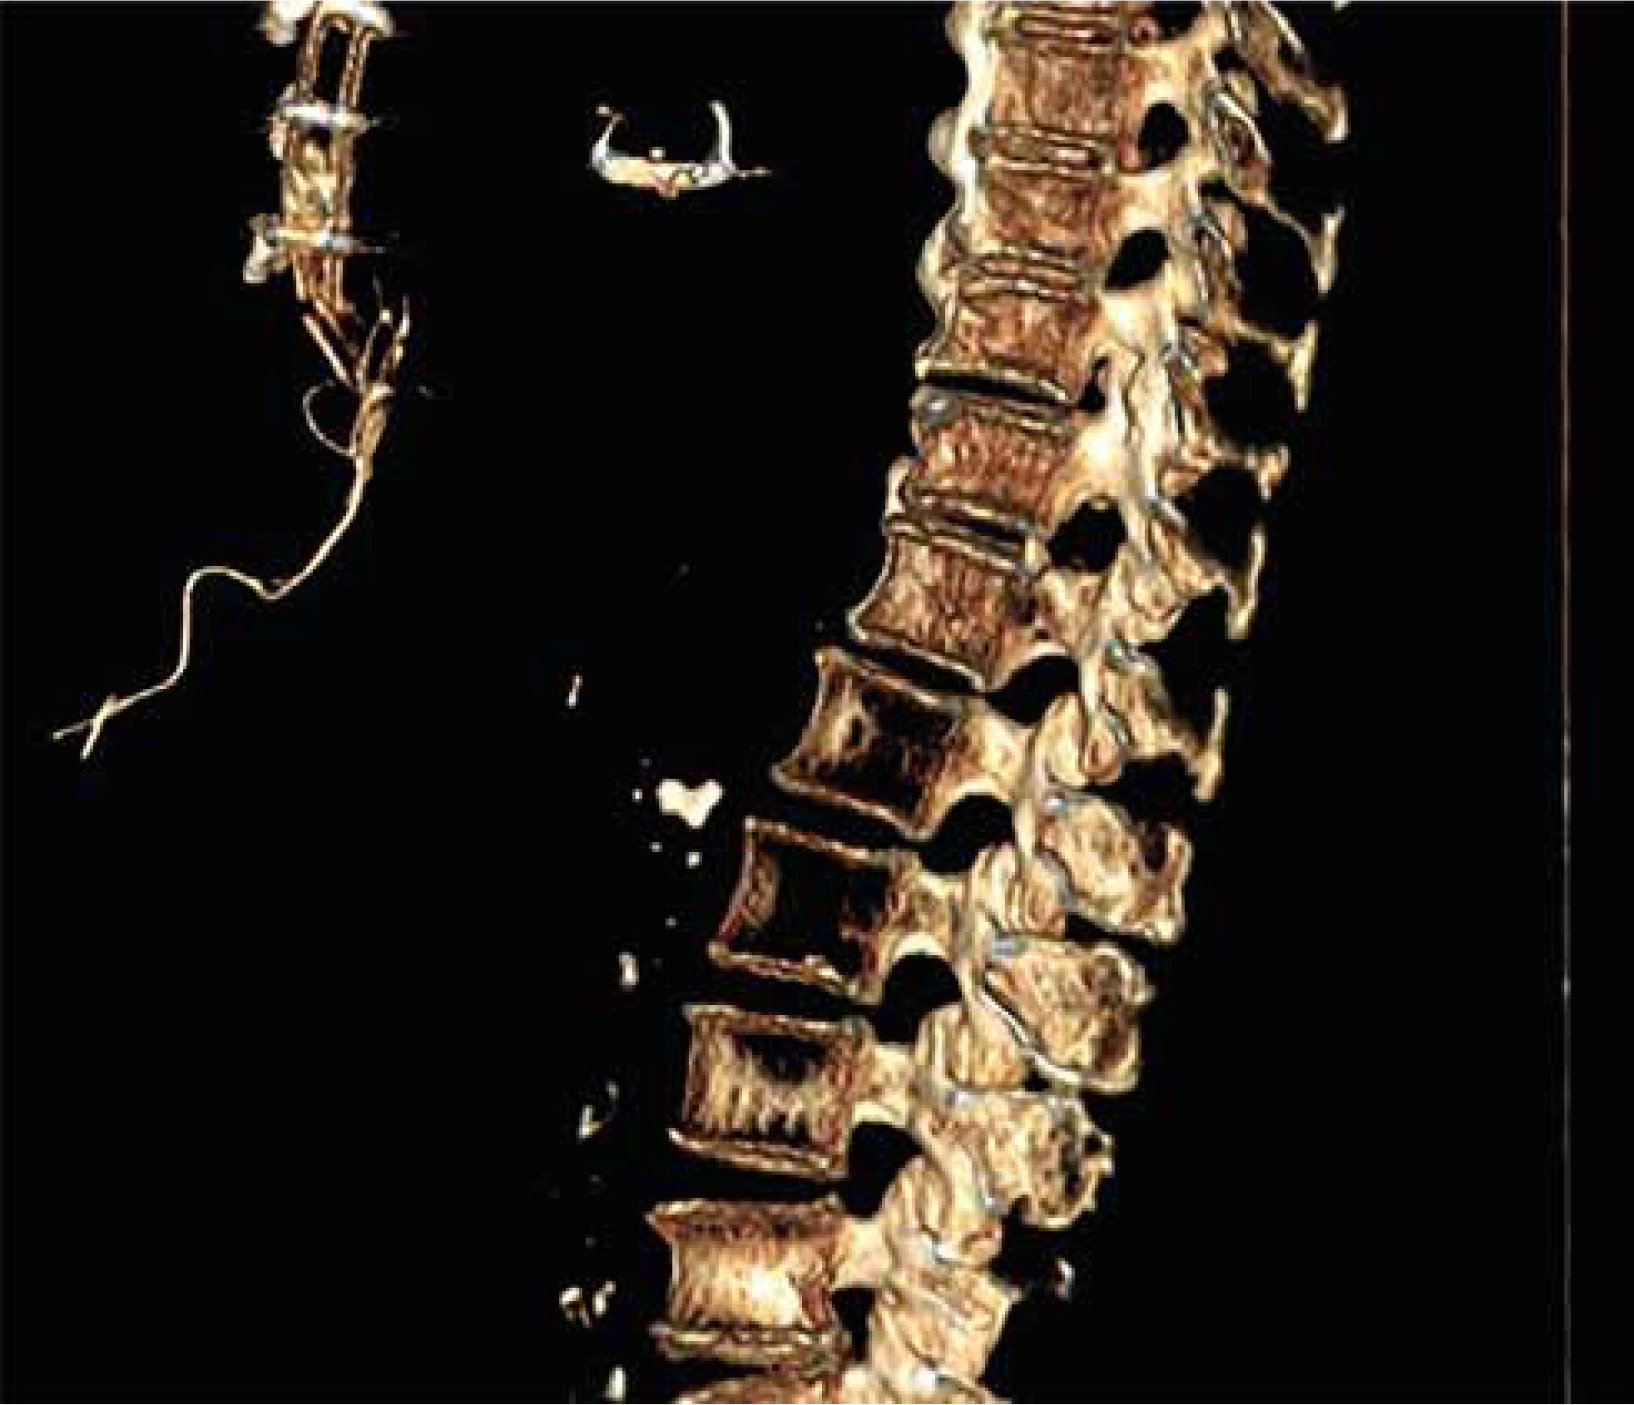

The patient did not develop fever but her blood count showed the normal range of hemoglobin, 11 g/dl, increase of white blood cell count, 12,500 per µl, and C-reactive protein level of 70 g/l. As the swelling kept draining and growing despite antibiotic therapy and serial medication, the patient was hospitalized once again in January 2019 to remove the granuloma surgically. During the post-operative follow-up the wound initially presented with a superficial dehiscence that eventually reached the deep edges of the wound; therefore a computed tomography (CT) scan was performed and it revealed the presence of a foreign body in the patient’s mediastinum which appeared to be the retained TEPWs (Figures 2–4).

Figure 2

Computed tomography (CT) scan images of the retained wires in the subcutaneous tissues of the patient (axial plane)